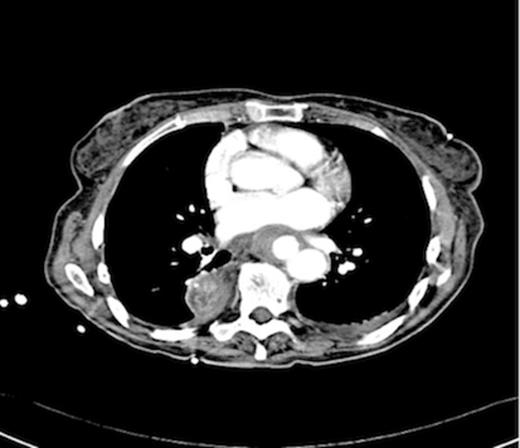

Post operatively the patient developed a low grade stent infection requiring a prolonged course of antibiotics as an outpatient. Two years after insertion of the stent she remains well with no further gastrointestinal bleeding and follow up endoscopy has shown intact mucosa at the site of fistula. Computerised tomography scanning has demonstrated involution of the aneurysm sac and no endo-leak (figure 5).